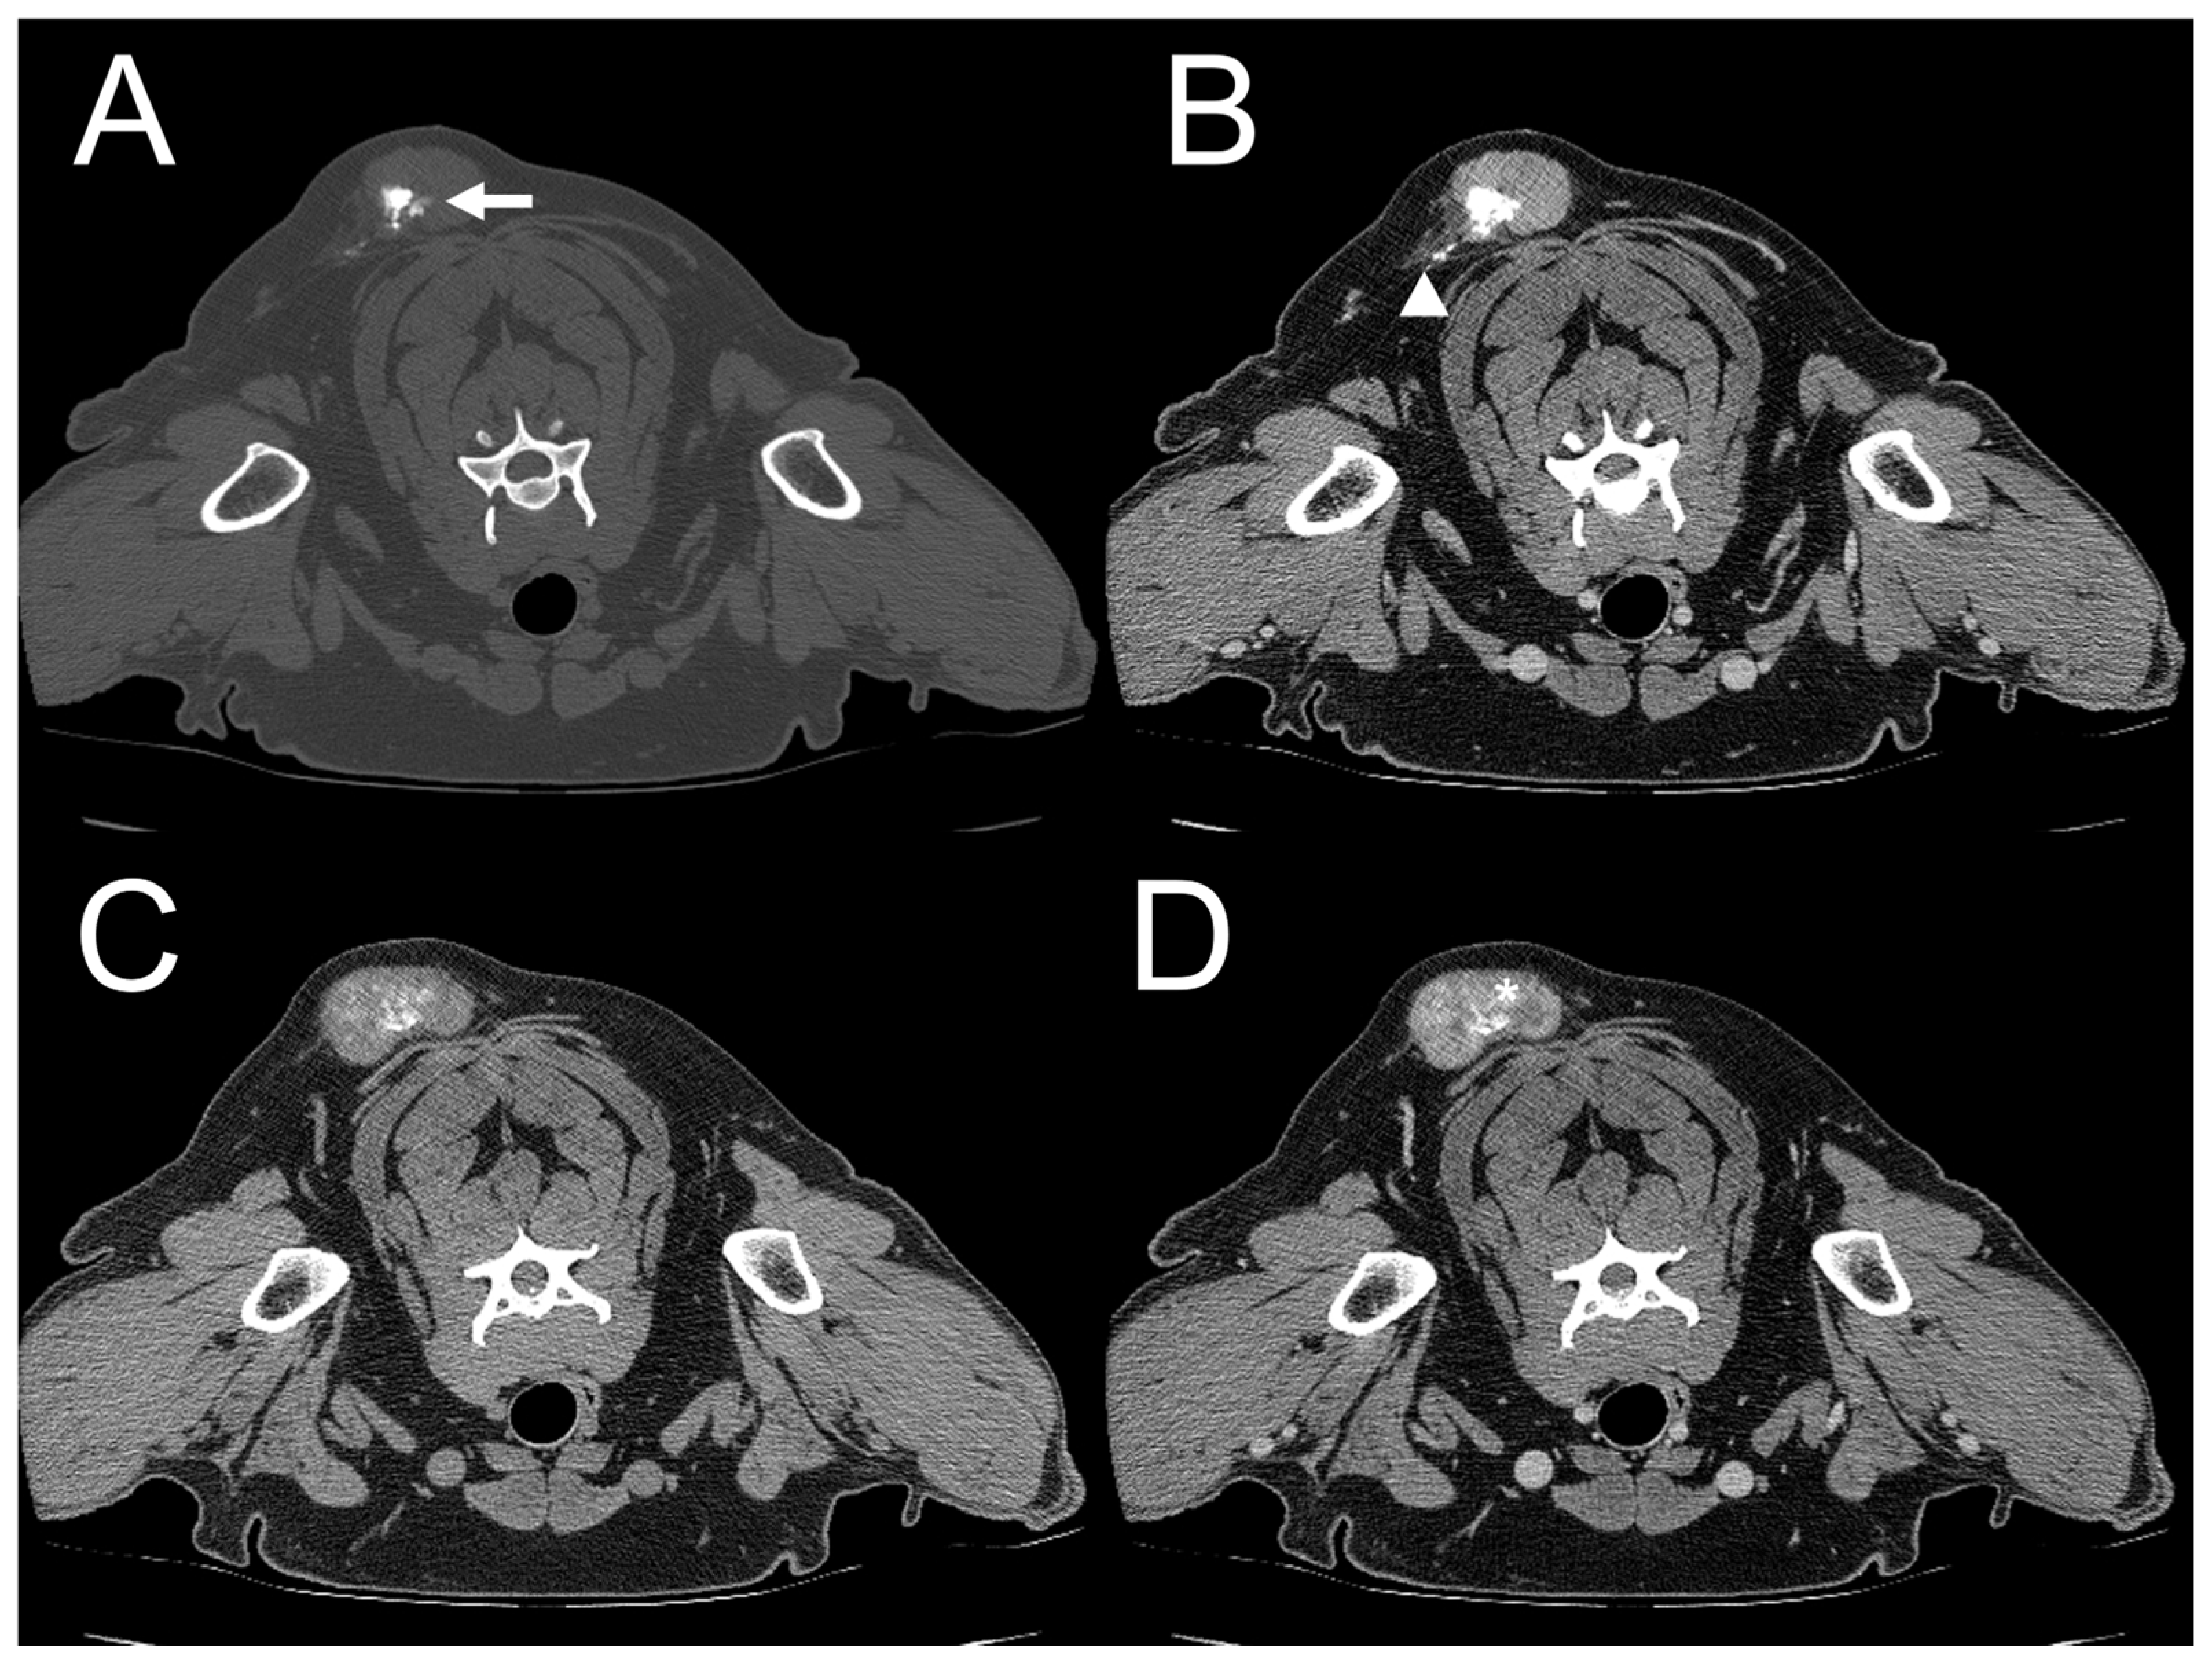

| Dog 1 | Subcutaneous (right parotid) | Ill-defined | Heterogenous | Absent | Present | Marked | Amorphous | Mixed |

| Dog 2 | Subcutaneous (right forelimb) | Well-defined | Absent | Present | Present | Moderate | Spindle | Mixed |

| Dog 3 | Subcutaneous (dorsum at level of the 4th–5th cervical vertebrae (C4–5)) | Ill-defined | Heterogenous | Absent | Present | Moderate | Amorphous | Mixed |

| Dog 4 | Subcutaneous (dorsum at the level of the 1st–8th thoracic vertebrae (T1–8)) | Well-defined | Heterogeneous | Present | Present | Moderate | Amorphous | Mixed |